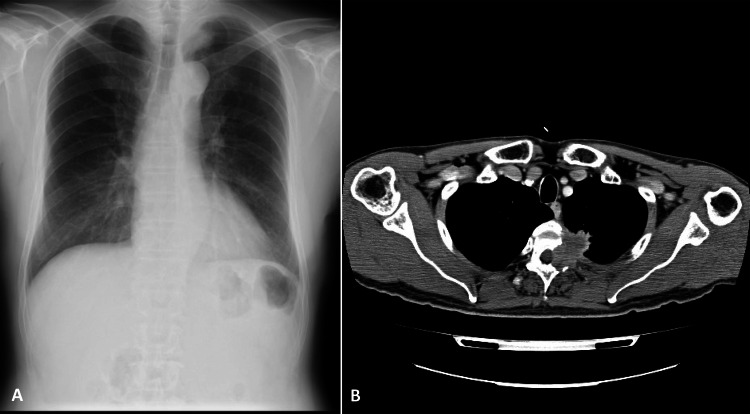

On physical examination, left constricted pupil (right: 3 mm; left: 2.5 mm) and ptosis and/or hypohydrosis in the left hemithorax were noted, suggesting Horner's syndrome. Light reflex was normal in both pupils. Neurologically, no sensory, thermic or pain deficits were noted. At the same time, chest x-ray (figure 1A) showed a mass in the left apical area measuring 3 cm in diameter. Contrast-enhanced thoracic CT (figure 1B) demonstrated a heterogeneous-enhanced mass as large as 3 cm located at the apical posterior wall along with the second to fourth ribs, which partially invaded the spinal canal area. He refused any invasive procedure, and was treated with radiation therapy under a tentative diagnosis of lung cancer T4N0M1b (Stage IV). Laboratory examinations were normal, except for mild elevation of serum squamous carcinoma antigen (1.9 ng/ml) and carcinoembryonic antigen (13.7 ng/ml).

Figure 1.

Chest x-ray (A) showing a mass in the left apical area measuring 3 cm in diameter. Contrast-enhanced thoracic CT (B) demonstrating a heterogeneously enhanced mass as large as 3 cm at the apical posterior wall, which partially invaded toward the spinal canal area.